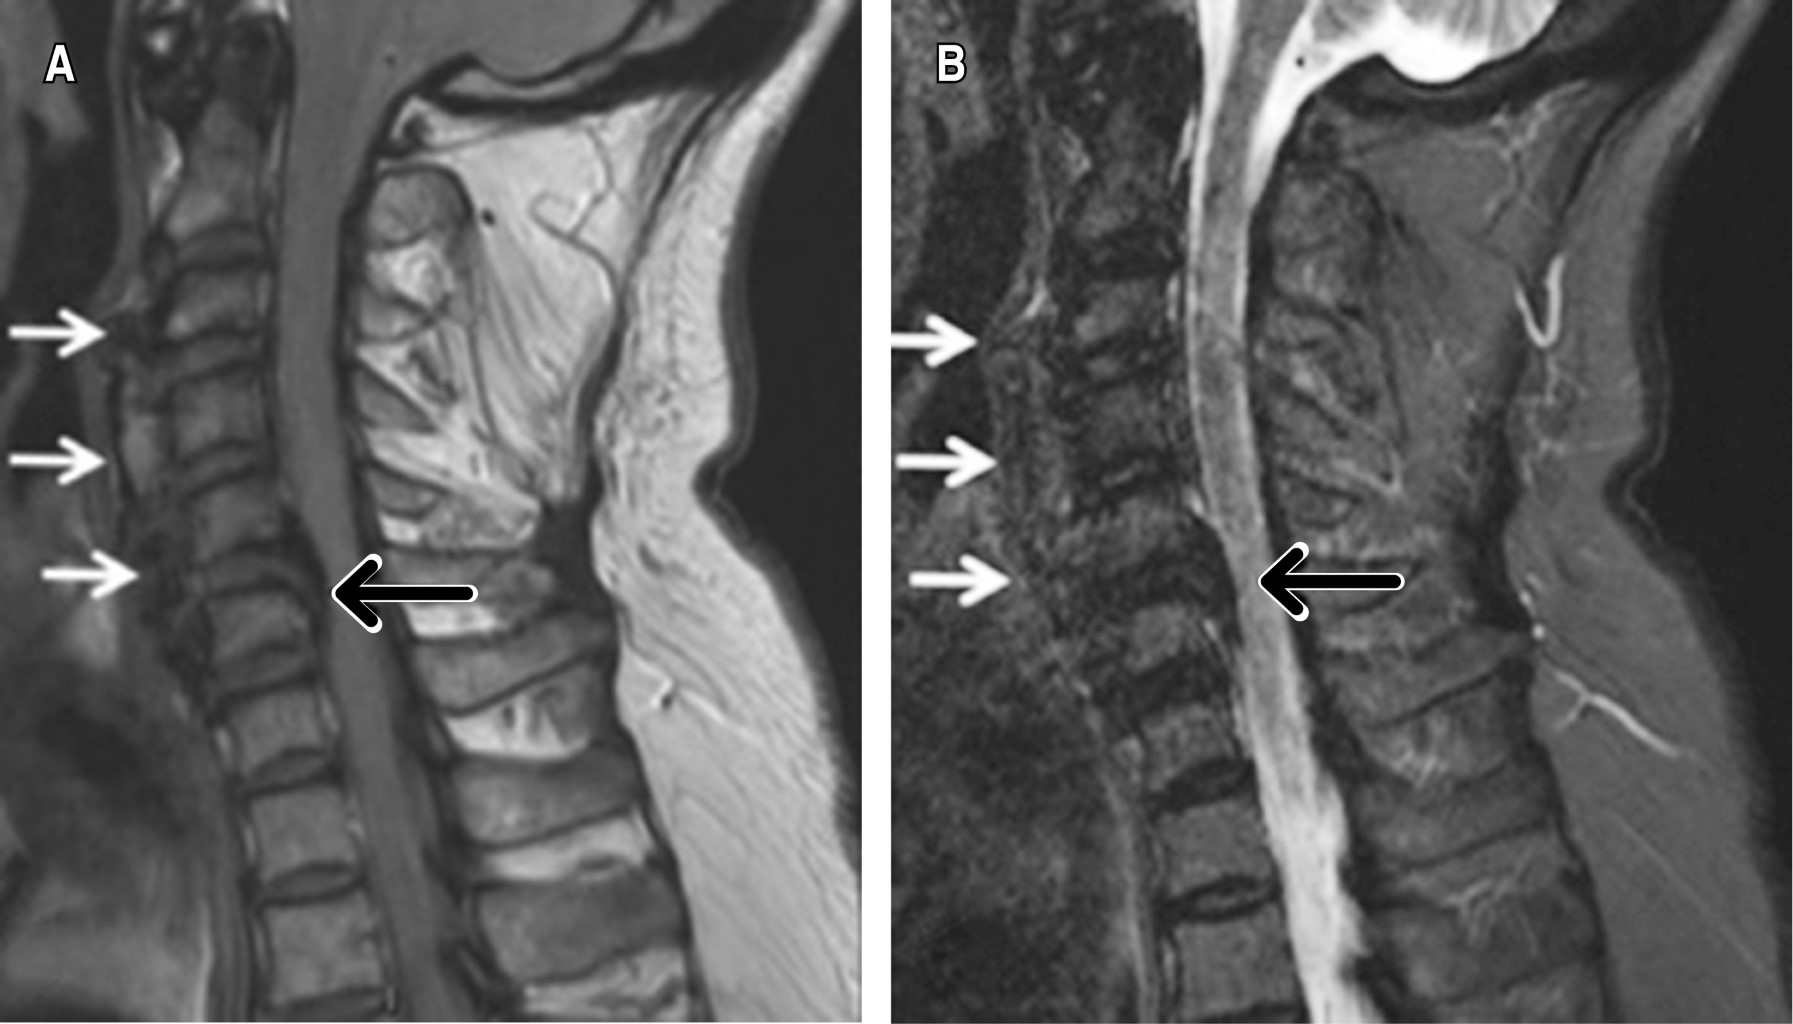

Debe considerarse DISH como factor de riesgo para fractura de columna cervical y deterioro neurológico asociadas a trauma menor.10 Previo al trauma menor las personas que cursan con DISH suelen ser asintomáticas. Sin embargo, en caso de presentarse, los principales síntomas son disfagia y obstrucción de vías respiratorias.11

El riesgo para fracturas cervicales es cuatro veces más frecuente en la columna anquilosada por DISH, teniendo alto riesgo de inestabilidad y lesión a la médula espinal asociada. Las fracturas más comúnmente encontradas en estos pacientes son de tipo hiperextensión (AOSpine-B3) y con desplazamiento (AOSpine-C).12

El diagnóstico de DISH en todos los casos se puede realizar con radiografías simples, aunque se pueden hacer estudios adicionales como TAC y resonancia magnética (RM).13

Cabe mencionar que las fracturas cervicales en DISH ocurren principalmente a nivel de los discos intervertebrales. La columna cervical es el segundo segmento más afectado, siendo C5 y C6 los cuerpos vertebrales más afectados.2,14

En el tratamiento de las fracturas cervicales es crucial la descompresión temprana para determinar el resultado clínico, inclusive si sólo hay como síntoma una disfagia leve preoperatoria.

Dentro del estudio de E. Okada y colaboradores se optó por manejo con fusión posterior. Se recomienda el manejo de tres niveles arriba y tres niveles abajo más debido a la mala calidad ósea, aflojamiento de material relacionado al manejo por vía anterior.13,15